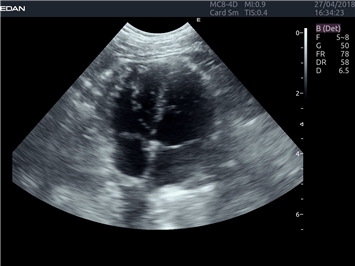

EDAN Acclarix LX4 VET

EDAN Acclarix LX4 VET представляет собой профессиональную ультразвуковую систему, специально разработанную для ветеринарных исследований. Сочетание стабильности, высокой производительности и эффективности делает эту систему идеальным выбором для современной ветеринарной практики.

Тканевой допплер:

Да

Анатомический М-режим:

M-режим: